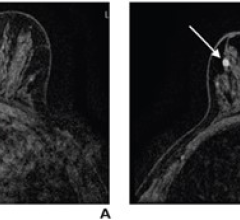

Koios SmartUltrasound is an AI-based software platform proven to accurately detect and diagnose both thyroid and breast cancers in ultrasound exams. Built using data sourced from a global network of partner sites, the technology aids physicians in quickly and accurately diagnosing disease, improving speed of interpretation, automating reporting, and reducing time to treatment, all while avoiding unnecessary surgical procedures. The increasing utilization of ultrasound in cancer detection, particularly for women with dense breast tissue, makes this innovation particularly relevant in today’s evolving healthcare landscape.